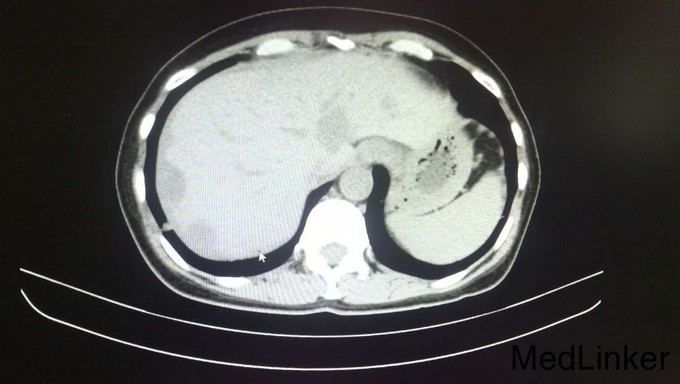

查体:腹平软,全腹部未扪及明显包块,全腹无压痛、反跳痛,右侧上中腹部可见一长约12cm的手术瘢痕,愈合良好,肝脾肋下未触及,墨菲氏征阴性,移动性浊音阴性,肠鸣音正常,无血管杂音。双肺呼吸音清,未闻及干湿性啰音,心脏听诊律齐,各瓣膜区未闻及明显病理性杂音。四肢查体无明显异常。 辅查:术后病理示:右半结肠中分化腺癌,部分为粘液腺癌,浸润肠壁全层,并侵犯神经组织,胰腺旁淋巴结见癌组织浸润并侵犯神经组织。2015年4月全身PET/CT检查示:右半结肠吻合口未见占位,纵膈1L组、肝门、腹膜后、右侧结肠旁沟淋巴结转移瘤,肝内转移瘤,胰头下方软组织转移瘤,双肺多发小结节,不排除转移瘤。2015年6月复查CEA:1353ng/mL,CA199:9674u/mL(较前明显升高)。其余重要影像学检查如下图所示: